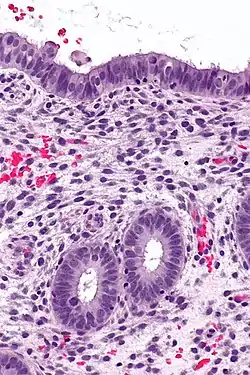

![]() Endometrium in the proliferative phase | |

The endometrium consists of a single layer of columnar epithelium plus the stroma on which it rests. The stroma is a layer of connective tissue that varies in thickness according to hormonal influences. In the uterus, simple tubular glands reach from the endometrial surface through to the base of the stroma, which also carries a rich blood supply provided by the spiral arteries. In women of reproductive age, two layers of endometrium can be distinguished. These two layers occur only in the endometrium lining the cavity of the uterus, and not in the lining of the fallopian tubes where a potentially life-threatening ectopic pregnancy may occur nearby.[4][5]

It is possible to identify the phase of the menstrual cycle by reference to either the ovarian cycle or the uterine cycle by observing microscopic differences at each phase—for example in the ovarian cycle:

| Phase | Days | Thickness | Epithelium |

|---|---|---|---|

| Menstrual phase | 1–5 | Thin | Absent |

| Follicular phase | 5–14 | Intermediate | Columnar |

| Luteal phase | 15–27 | Thick | Columnar. Also visible are arcuate vessels of uterus |

| Ischemic phase | 27–28 | Columnar. Also visible are arcuate vessels of uterus |